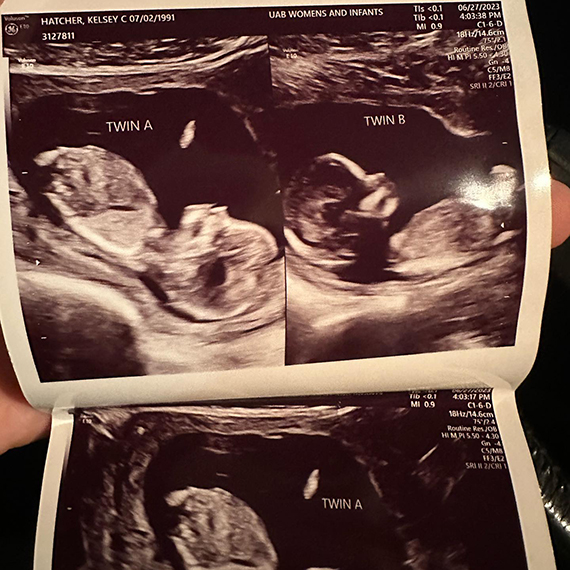

ABD’de yaşayan Kelsey Hatcher isimli bir kadın, doğuştan çift rahmi olduğunu ve nadir görülen bir hamilelikle her iki rahminde de kız bebek beklediğini duyurdu. Hatcher’ın doktoru, genç kadının iki rahminde iki ayrı bebeğe aynı anda hamile kalmasının milyonda bir olduğunu ifade etti.

ABD’nin Alabama eyaletinde yaşayan 32 yaşında, üç çocuk annesi Kelsey Hatcher, uterus didelphys veya iki uterus adı verilen nadir bir uterus anomalisiyle doğdu. Hatcher basına verdiği röportajda, geçen baharda hamile olduğunu öğrenene kadar böyle bir ihtimal olabileceğini bilmediğini ifade etti.